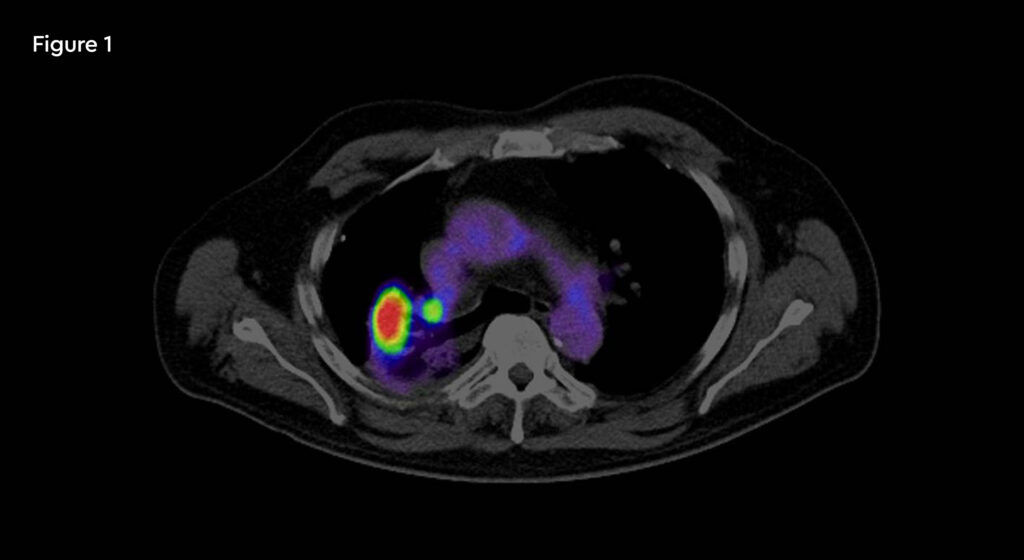

Figure 2: Contouring target lesion

At each session, daily adaptation was performed to account for changes in the position of the prostate and for variable bladder and bowel filling. Figure 1 and figure 2 illustrate the typical differences seen between the original planning MRIdian scan and that seen on the day of treatment due to day-to-day organ movement. Figure 3 and figure 4 illustrate how these movements were accommodated with the on-table plan adaptation.

Figure 1 and figure 2 illustrate the typical interfraction movement as seen on the MRI scan. Figure 3 and figure 4 demonstrate the daily changes of the patient’s internal anatomy whilst figure 5 and figure 6 show the adaptive radiotherapy plan.